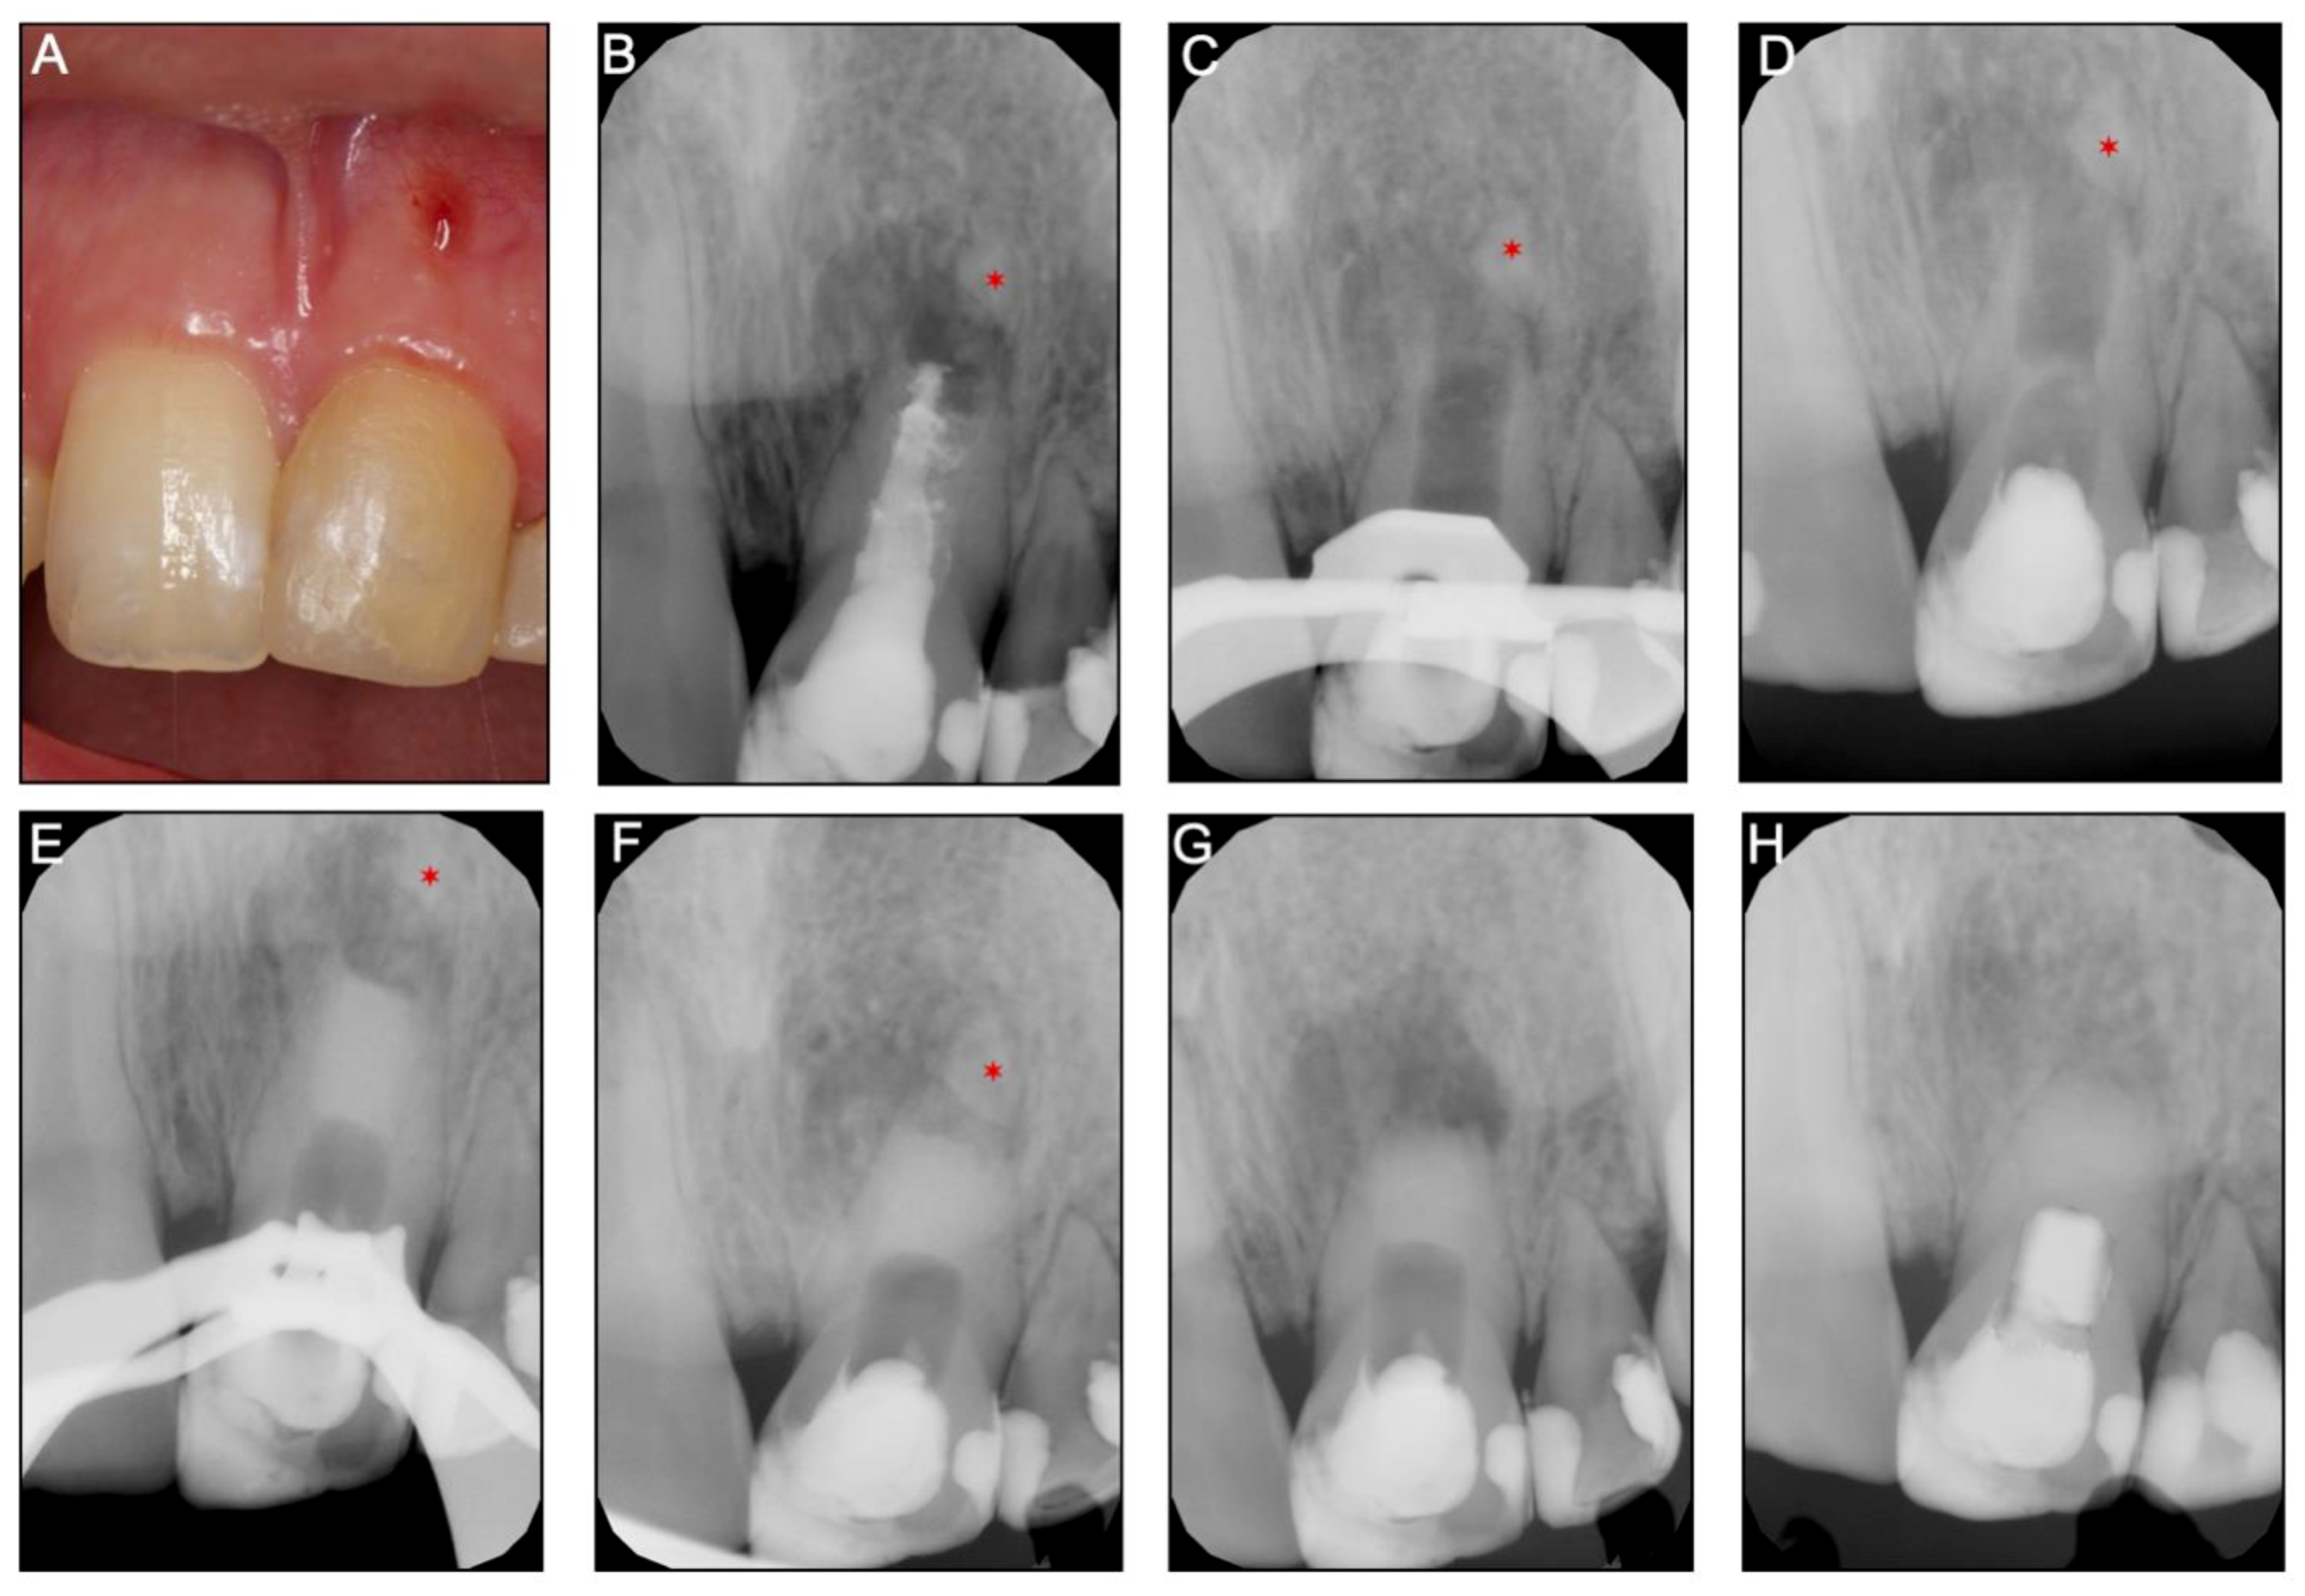

2.2. Case 2

A 16-year-old girl was referred for the nonsurgical endodontic retreatment of the maxillary left central incisor (21) with pulp necrosis and chronic apical periodontitis with the presence of a long-standing sinus tract and a previous endodontic treatment failure. The periapical radiograph and CBTC revealed the maxillary left central incisor with pulp chamber and the canal underfilled with core material and a mineralized tissue beyond the tooth apical portion, separated from the root (Figure 3A,B and Supplementary Materials: Video S2). The agenesis of several teeth was confirmed (12, 22, 32, and 42) with the patient records. Previous dental trauma (non-specified on the parent’s records) on tooth 21 at age 7, followed by an attempt of REP by a generalist dentist, two years before the visit was referred by the child parents. However, the patient remained with edema, swelling, and a sinus tract associated with tooth 21. At the day of evaluation, tooth 21 had normal periodontal probing, and response to sensibility tests (thermal and electrical pulp testing) was negative. After an extended discussion with the children parents about the several treatment options, a nonsurgical root canal retreatment with an apical barrier with a biomaterial (BiodentineTM, Septodont, Saint-Maur-des-Fossés Cedex, France) was elected.

At the first appointment, anesthesia was performed with 3% mepivacaine (Mepivastesin®, 3M ESPE, Neuss, Germany) and under the rubber dam, an access cavity was made with a diamond bur (size #12, Dentsply Sirona, Ballaigues, Switzerland) and refined with an Endo-Z drill (Dentsply Maillefer, Ballaigues, Switzerland). After accessing the pulp chamber, a previous root filling was removed under magnification. Then, a long-neck (LN) bur (size #10, Dentsply Sirona, Ballaigues Switzerland) and an ultrasonic tip (size #3, Start-XTM, Dentsply Sirona, Ballaigues Switzerland) were used to remove the hard material from the canal walls, which was similar to a hydraulic silicate cement (Figure 3C). The same tip was used for ultrasonic agitation of the irrigant. After minimal manual instrumentation with a K-file (size #50, Dentsply-Maillefer, Balaigues, Switzerland) of the canal walls, the disinfection procedure was achieved with copious irrigation of 3% sodium hypochlorite (NaOCl; CanalProTM, Coltène/Whaledent, Langenau, Germany). Intracanal medication (45% CH, Calcicur) was placed in the coronal portion of the canal (Figure 3C) and the access cavity closed with a temporary restorative material (CavitTM).

Three weeks later, the tooth (21) was asymptomatic, and no edema or sinus tract were observed. In the second session, local anesthesia was performed with 2% lidocaine with 1:100,000 epinephrine (XylesteinTM 2%, 3M ESPE, Neuss, Germany), a rubber dam placed, and the provisional material was removed.

The intracanal medication was removed with continuous irrigation of 3% sodium hypochlorite (NaOCl; CanalProTM, Coltène/Whaledent, Langenau, Germany) and saline solution. The canal was dried with paper points and a bioceramic material (BiodentineTM) was prepared in accordance with the manufacturer’s instructions. It was smoothly carried into the canal and compacted apically with a hand barrierger (size #2, Buchanan Hand Plugger) to form an apical barrier of 5 mm in thickness. The excess of material from the walls was removed with paper points, a moist cotton pellet was added, and the access cavity was temporarily closed (CavitTM). Intraoperative and postoperative radiographs were taken to confirm the apical barrier position.

After 2 weeks, the patient developed spontaneous pain, swelling, and a sinus tract. At this time, the surgical endodontic treatment was proposed and explained to the patient and parents. After informed consent was obtained, the surgical procedure was performed by the same Endodontist who performed earlier the apical barrier. Anesthesia was achieved with 2% lidocaine with 1:80,000 epinephrine (XylestesinTM, 3M ESPE, Neuss, Germany), and an Ochsenbein Luebke flap was raised. Following flap retraction, the lesion was accessible and the granulation tissue was carefully removed by curettage. Approximately 2 mm of the root-end was resected with a surgical bur in an air impact high-speed handpiece. After root-end resection (~2 mm), the previous Biodentine barrier was inspected under magnification—nor voids nor chromogenic pigmentation or discoloration detected—as well as mechanically tested with a probe to evaluate its resistance and the lack of voids showing a well condensed barrier and for these reasons no retrograde root-end filling was done. The flap was repositioned and sutured (Figure 3G). One week later, the patient returned with no signs or symptoms, and a resin-based composite (SDRTM flow and Spectrum®) was placed into the root canal structure above the apical barrier all the way to the incisal edge. The resected apical root portion was processed for histologic evaluation. Histopathological assessment of the apical root fragment removed during the surgical root canal treatment was performed (Figure 4). Staining with hematoxylin and eosin (H&E) depicts the presence of a root tip, with pulp tissue at the main foramen as well as small foramina, surrounded by dentin and cement. The presence of a giant multinucleated cell in the pulp tissue near the major foramen shall be emphasized. Granulation tissue was observed in and around the excised root tip.

A 5-year follow-up after endodontic surgery as well as clinical and radiographic (Figure 3H) examination revealed almost complete apical healing and healthy soft tissues.

Figure 3. Clinical and radiographic images of Case 2 of teeth 21 with endodontic treatment failure. (A) Initial photograph showing the presence of a sinus tract. (B) Initial radiographic depicting a periapical radiolucency. The periapical radiograph revealed the maxillary left central incisor with pulp chamber and the canal underfilled with core material and a mineralized tissue beyond the tooth apical portion, separated from the root (*). (C) Nonsurgical root canal retreatment was used to remove the hydraulic silicate cement from the canal walls. (D) Periapical radiograph after the access cavity was closed with temporary material, and the intracanal medication (CH, Calcicur) was placed in the coronal portion of the canal. (E) An operative and (F) and postoperative to confirm the apical barrier position. (G) Postoperative radiograph after the surgical procedure. (H) Five-year follow-up after endodontic surgery.